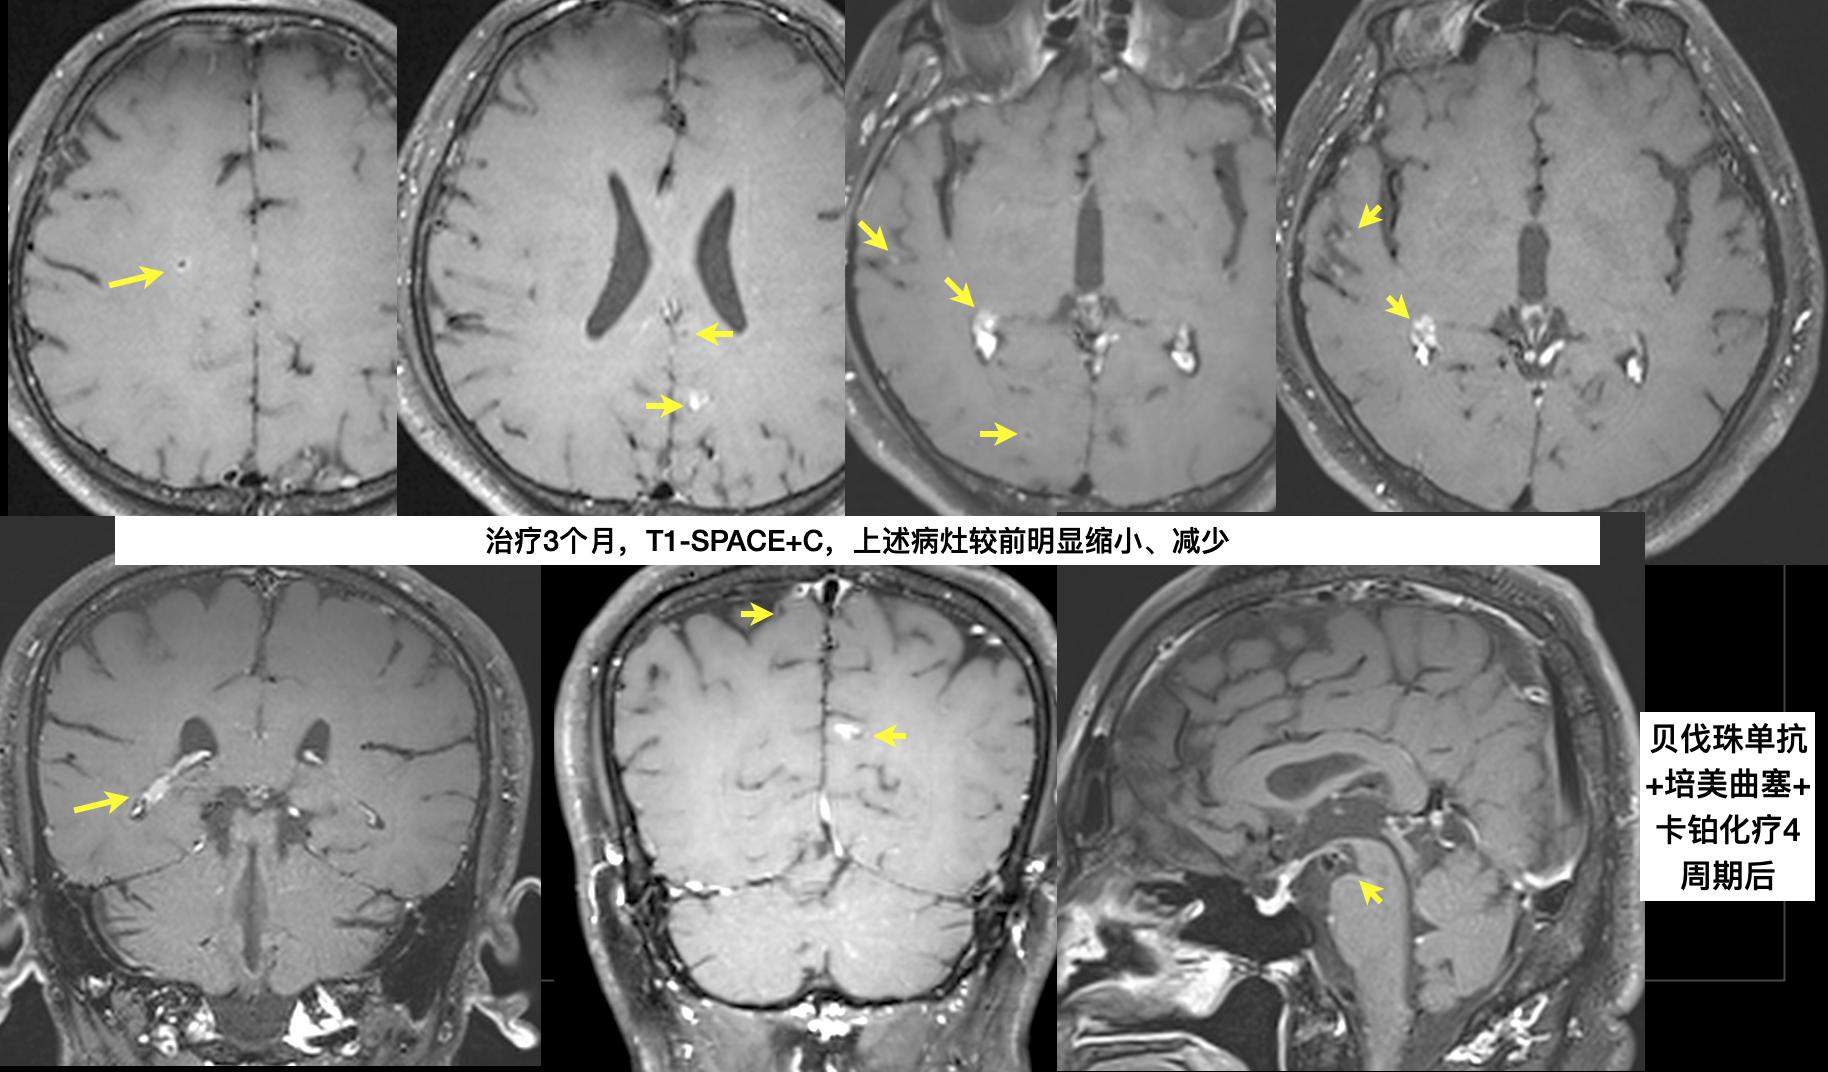

贝伐珠单抗+培美曲塞+卡铂”化疗3个月后复查,脑病变好转